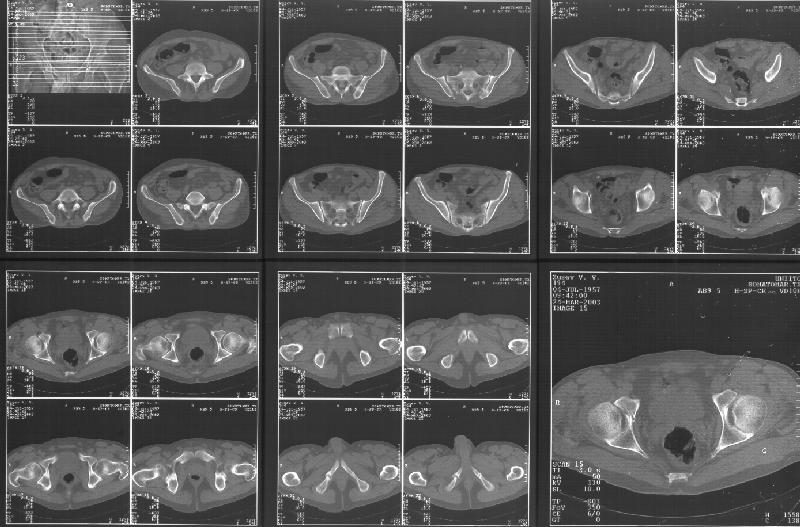

Прилагаю свежую КТ таза.

Буду признателен за комментарии и предложения по тактике.

Картинки см. ниже, левая - с экранным разрешением, вторая - полноразмерная, ~900 кб.

КТ в экранном разрешении